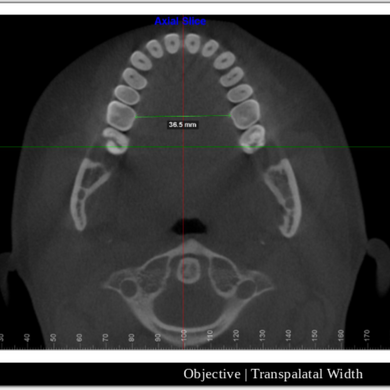

If you are suffering from high blood pressure, heart disease, or epilepsy, your dentist or sleep apnea expert can recommend you the diagnostic examination to look for sleep apnea disease. Physical examination for adults includes measuring for a wide neck, looking for enlarged tonsils, and assessing upper body obesity. In children examination, a doctor examines for the enlarged adenoids and confirm if your child has deficit issues.